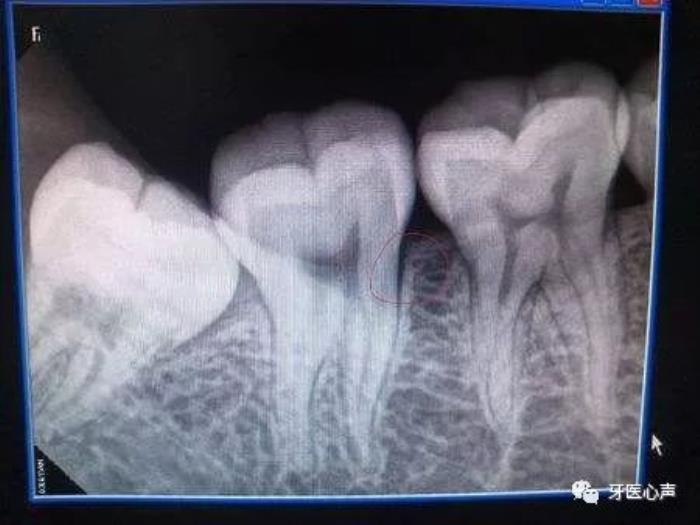

不愿意拍牙片

一些患者不愿意照牙片,认为医生拿眼睛就可以检查了啊。医生的眼睛不是透视镜啊,牙齿好比大树,树根扎在土壤里,而我们的牙根也埋在牙槽骨里,牙根的状态、里面的神经肉眼都是看不到的。只有通过牙片,牙医才可以确切了解龋坏的范围、牙痛是由牙髓炎还是根尖炎或是牙周炎引起、种植牙需要的骨量等等。牙片为医患沟通提供了准确的依据。

有些家长还认为孩子拍牙片会受到辐射,对身体不好,其实大可不必担心,牙科X光片对身体辐射量相当低,并且正规牙科都会配备防辐射服,影响几乎微不足道。